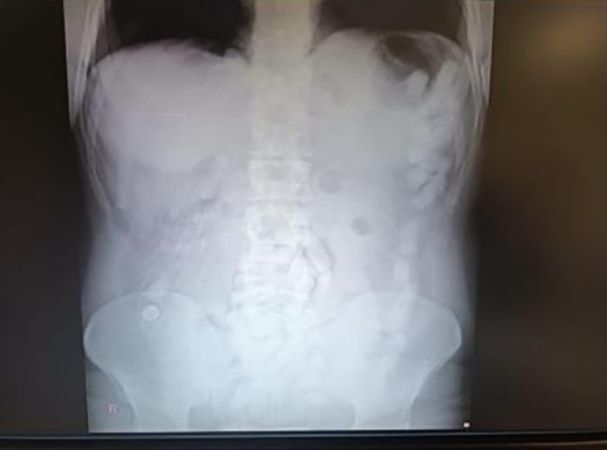

4 Mayıs 2024’te Kayseri İl Emniyet Müdürlüğü Narkotik Suçlarla Mücadele Şube Müdürlüğü ekipleri, yabancı uyruklu A.H.’nin ülkeye giriş yaparak üzerindeki uyuşturucu maddeleri Kayseri’ye getireceğini tespit etti. Şahsı takibe alan ekipler, yerini belirledikten sonra operasyon düzenledi. Kayseri Şehir Hastanesi’nde ultrason çekimi ile yapılan kontrolde şahsın midesinde çok sayıda kapsül olduğu belirlendi. Yapılan operasyonla şahsın midesinden çıkarılan 100 kapsülün içinde toplam 729 gram uyuşturucu madde ele geçirildi.